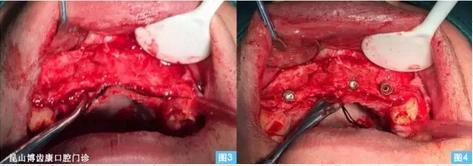

圖3圖4:(左圖3)牙槽嵴頂偏腭側(cè)水平切口,雙側(cè)附加切口翻開全厚粘骨膜瓣至鼻底,清晰暴露術(shù)區(qū)。(右圖4)小球鉆定位,擴孔鉆依次備洞,植入植體 ,可見13、23唇側(cè)骨壁缺損嚴重 。